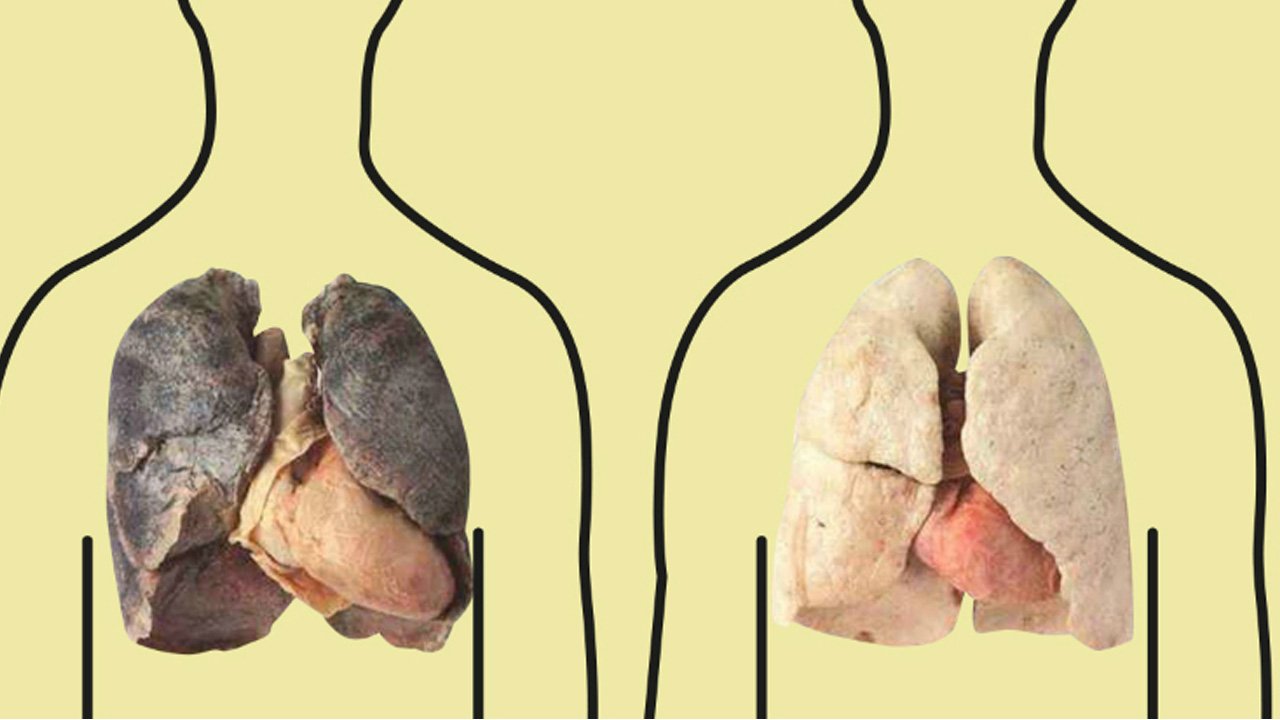

Здоровые Легкие Картинки

Здоровые Легкие Картинки 117 фото